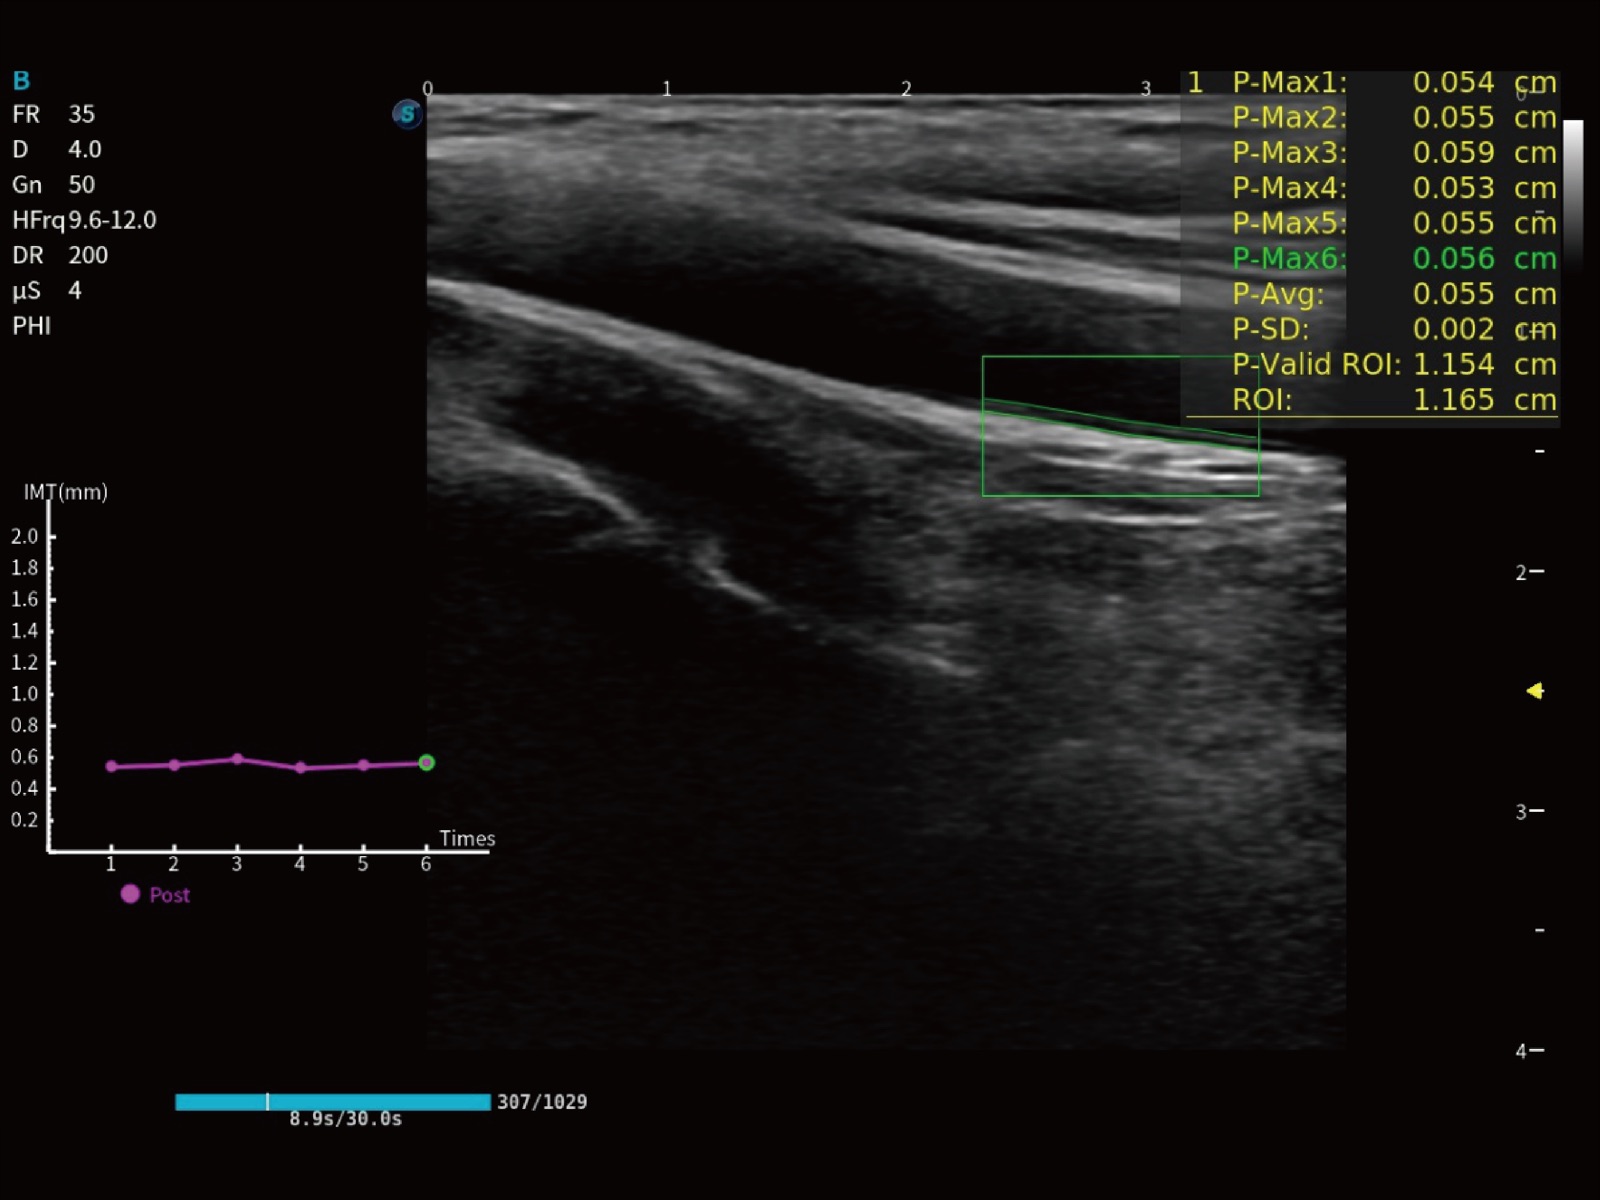

E11搭载了丰富的自动化测量工具,以及专为POC科室定制的高级功能;同时配备了为急诊医师量身打造的 SonoFast急重症超声流程,以帮助临床医生最大限度的提升工作效率